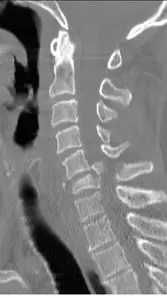

頸椎的 CT影像如下圖,下列何者為最有可能之診斷?

- 影像切面與造影條件:這是一張頸椎的無顯影劑電腦斷層矢狀面重組影像(Sagittal CT reconstruction),且使用**骨骼窗(Bone window)**來呈現,此設定最適合用來評估骨骼結構的完整性與皮質骨的連續性。

- 解剖定位(節數計算):

- 尋找定位地標:在影像最上方,可見一個明顯向上凸出的柱狀骨頭,這是頸椎第二節(C2,樞椎 Axis)的齒狀突(Dens / Odontoid process)。

- 齒狀突正下方的方形骨頭即為 C2 椎體。

- 從 C2 椎體開始依序向下計算:C3、C4、C5 椎體的外觀皆呈現方正且皮質骨邊緣完整。

- 當數到 C6(第六節頸椎) 時,可發現該椎體發生了嚴重的結構破壞。

- 病灶特徵:

- C6 椎體出現明顯的銳利骨折線(Fracture line),椎體的前下緣有一塊三角形的游離骨碎片(呈現典型的**屈曲型淚滴狀骨折 Flexi